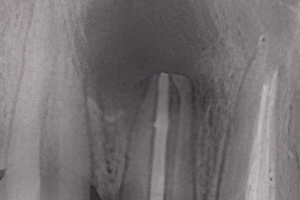

Трудности в лечении этого зуба связаны с тем, что его мезиодистальная ширина намного меньше (Рис. 1А) по сравнению с вестибулярно-язычной шириной (Рис. 1В), что делает очень трудным, если не невозможным, расширение канала или каналов полностью в любом направлении.

Рисунок 1. A. Нижний центральный резец. Обратите внимание на малую мезиодистальную ширину корня. B. Корень того же зуба значительно шире в вестибулярно-язычном направлении. Обратите также внимание на вогнутость на уровне средней трети.